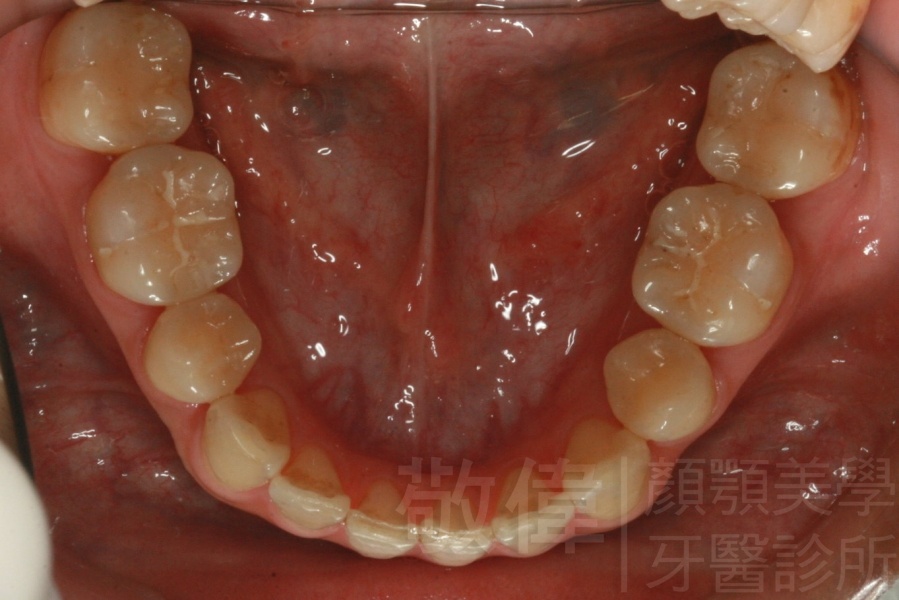

變臉矯正,原來戽斗妹跟大歪臉變成自信正妹

經由本院3D數影X光影像儀分析、與3D齒顎顏矯正技術,再配合口腔顎面正顎專科醫師施以正顎手術治療,雙方共同合作,使患者臉部外觀有很好的改善,大歪變小歪,產生了天南地北的大改變,她的人生也整個變得不一樣。

因為矯正與正顎手術的配合,使「戽斗妹」變成了「陽光正妹」,完全的改變了她的人生,在面對各種場合、與人交際都散發出自信微笑。所以,奉勸家長,如果小朋友有臉顎畸型的問題,應該考慮配合做這種簡單、安全、有效的正顎手術。